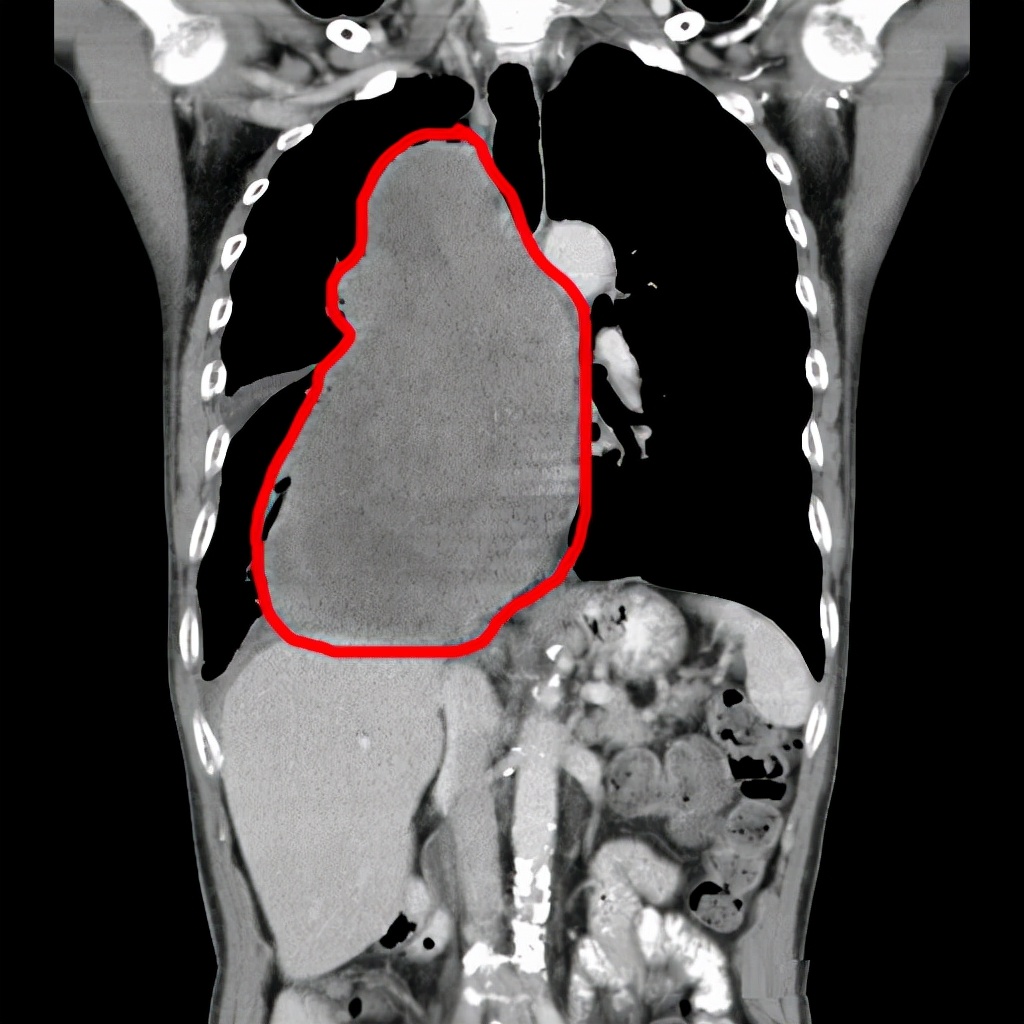

入院后,张先生完善相关检查,CT显示其脊柱右侧旁有一大小约14.4×9.7×22.7cm的巨大团块状软组织密度影 。 “耽搁了一个月肿瘤就从7cm长到22.7cm,当时我院医疗一科钱伟主任说我父亲吃不下饭呼吸困难是因为肿瘤太大挤压支气管与食道,如果再晚来个三四天情况会更严重 。 ”

为了控制肿瘤的发展,入院5天后张先生接受了右肺肿瘤穿刺活检和右肺部分肿瘤微波消融术,但因送检的病理标本是大量坏死和细胞碎片,并未能确切肿瘤性病变 。 为了明确诊断,我院再次为张先生实行右肺肿瘤穿刺活检,结果为右肺小细胞肺癌广泛期 。

针对张先生的情况,我院介入科杨清峰与钟小军医师分别为他实行了3次介入治疗 。 影像资料显示,张先生肿瘤有所缩小,疗效评价为PR 。 (PR——部分缓解,肿瘤最大直径及最大垂直直径的乘积缩小达50%,其他病变无增大,持续超过1个月 。 )